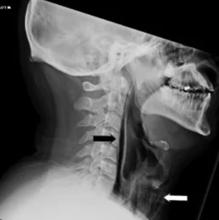

Los investigadores explicaron que un hombre de 34 años acudió a urgencias. Dijo que había notado un crujido después de un potente estornudo reprimido y que su cuello había comenzado a hincharse. El hombre casi había perdido la voz y pudo contar que le resultaba extremadamente doloroso tragar.

Las exploraciones encontraron burbujas de aire en los músculos de la caja torácica, una condición que se llama pseudo mediastino. El paciente fue ingresado en el hospital para recibir antibióticos (y evitar posibles infecciones a causa de las burbujas) y alimentación intravenosa para no tragar. Finalmente, se recuperó después de una semana.

El motivo de sus lesiones está en que la presión generada con el estornudo no pudo liberarse a través de la boca y la nariz. En lugar de eso, la fuerza dañó los tejidos blandos de la garganta. De hecho, rompió la faringe , la cavidad membranosa que une el esófago y la laringe con la boca y la nariz y que funciona como una caja de resonancia para el habla.